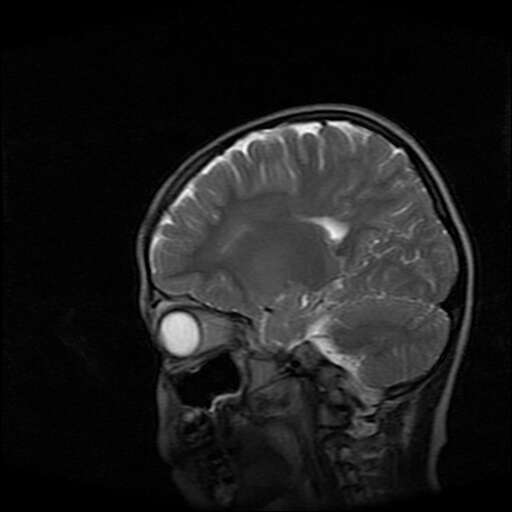

女,7岁,三岁才说话、走路。现智力尚可,走路不稳。临床怀疑大脑发育不全。

考虑 脑白质发育不良

脑折质变薄,双侧侧脑室稍扩张,支持考虑脑折质发育不良

侧脑室周围白质软化症。

考虑胼胝体发育不全,髓鞘形成不良。

支持考虑胼胝体发育不全,髓鞘形成不良。

脑裂畸形伴灰质异位

侧脑室周围白质数量减少,侧脑室不对称性扩大,左侧侧脑室后角呈方形改变,脑沟加深,结合临床考虑脑室周围白质软化症(pvl)。期待结果!

只看出灰质异位

支持脑白质发育不良。